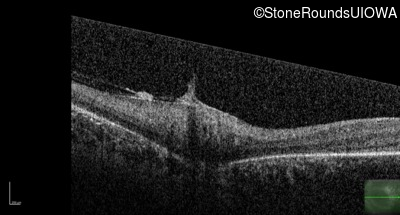

Optical Coherence Tomography - Right - No Light Perception

Exemplar / OCT Stack